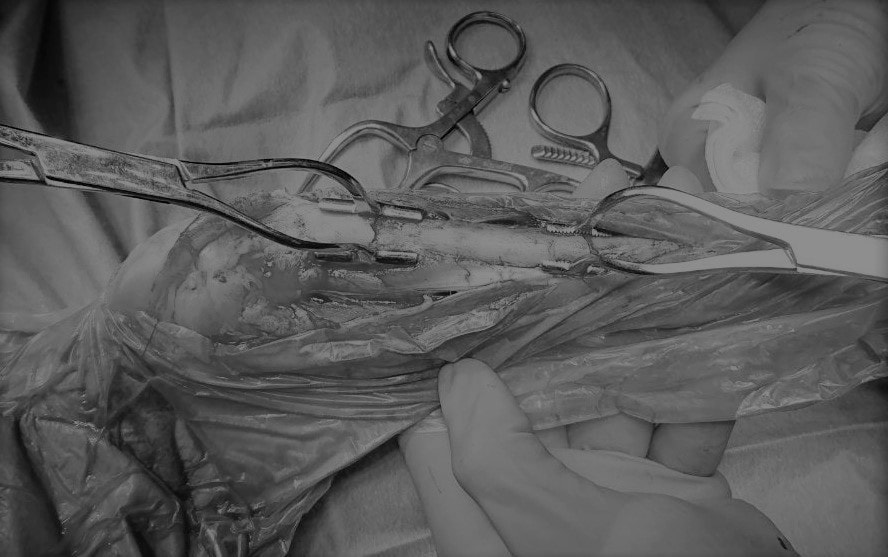

症例3:キルシュナーワイヤーのピンニングによる整復

ペルシャ猫 11ヶ月齢 雄

他院にて左大腿骨遠位の成長板骨折(salter-harrisⅠ型)が認められており、治療相談を目的として来院。当院にて、キルシュナーワイヤーを用いたピンニングにより骨折部位の整復を行いました。術後の経過は良好で、現在も経過観察中です。

Arthrex社のターゲティングデバイスを用いてピンニングの位置を調整することで、確実な固定を行っています。当院ではこの手術器具以外にも、人の手術にも使用される様々な器具を導入し、手術精度を高め、また医療メーカーと新しい器具の開発、試作にも取り組んでおります。